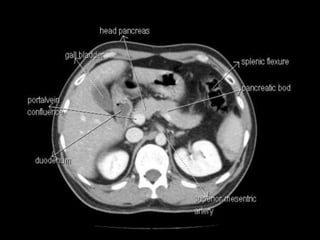

Cross section anatomy of abdominal ct scan

Cross section anatomyof abdominal ct scan